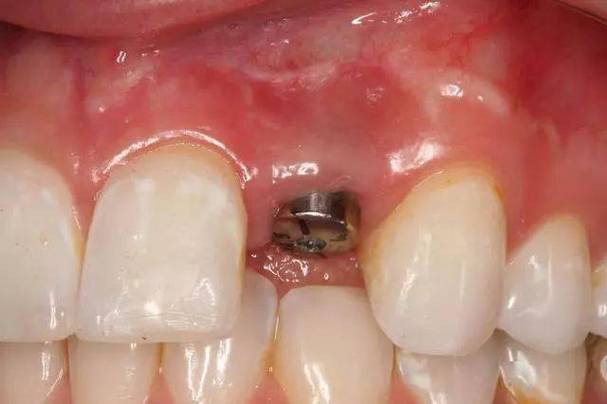

异常暴露:病理性风险信号

若种植体本体(非基台部分)暴露,或基台暴露伴随牙龈红肿、出血、溢脓等症状,则属于异常暴露,可能由以下原因导致: